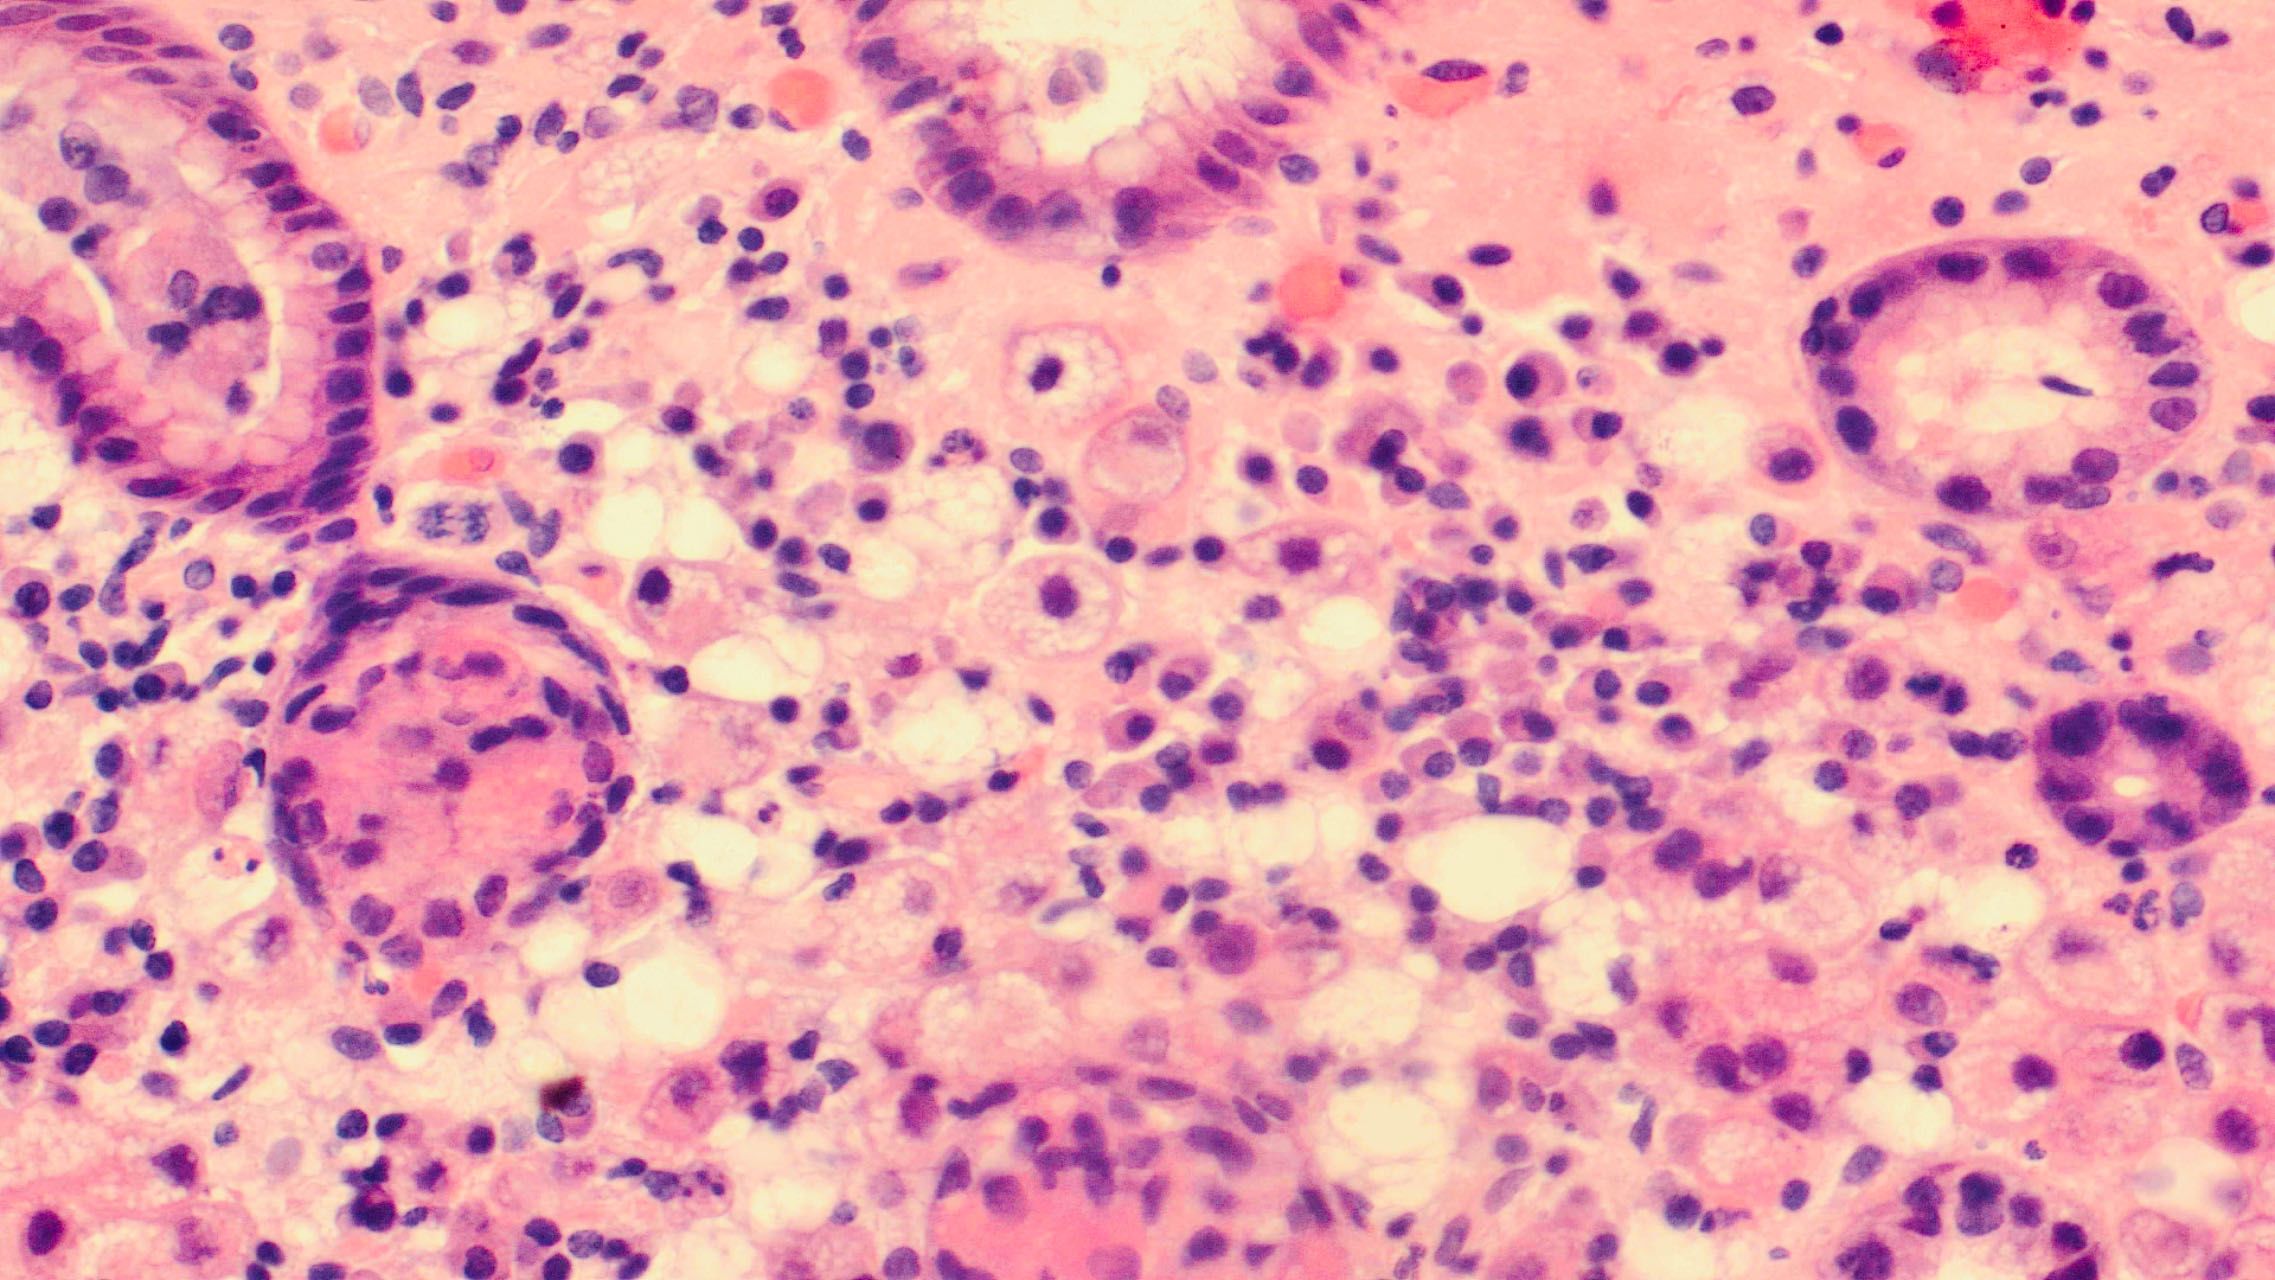

继续放大

等等、等等。。。这是什么?浆细胞?组织细胞?印戒细胞?

印戒细胞是这样的

组织细胞是这个样子

病理科医生觉得都不像啊,怎么办?做免疫组化标记一下吧!

经过免疫组化,怀疑的细胞上皮标记物被标记出来了,最后诊断:胃低分化腺癌,后来手术标本全部的病灶只有1CM !